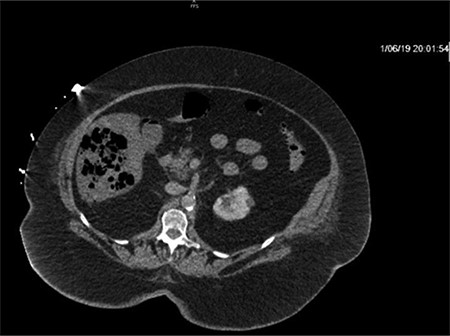

Repeat CT demonstrated a large amount of air within the liver parenchyma (Figs 2, 4, 6). Unfortunately, shortly after the repeat CT, the patient progressed to septic shock with cardiovascular collapse and was not able to be resuscitated with full advanced cardiac life support (ACLS) protocol. She expired within 16 h of initial presentation and within 24 h of symptom onset. Final blood culture results were positive for Clostridium perfringens.

Repeat imaging taken 13.5 h later which depicts many air bubbles in the liver parenchyma.